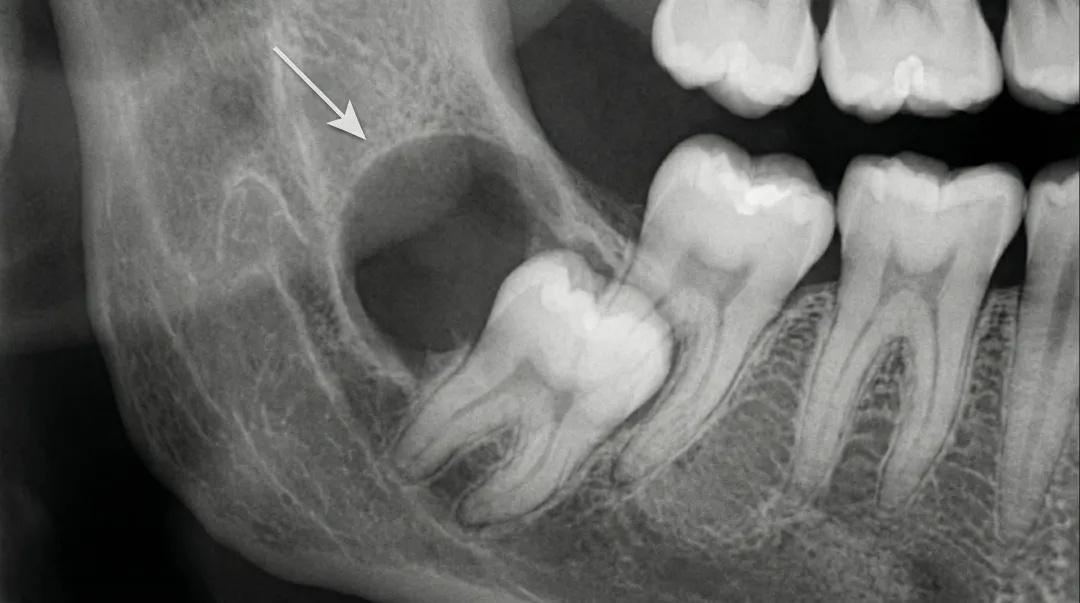

Impacted Wisdom Teeth

Impaction occurs when wisdom teeth cannot fully emerge through the gums due to insufficient space or improper positioning. The American Association of Oral and Maxillofacial Surgeons reports that nine out of ten people have at least one impacted wisdom tooth.

The three main impaction types include:

- Angular impaction - Tooth tilts toward neighboring molars (most common at 41.8% of cases)

- Horizontal impaction - Tooth lies sideways in the jawbone

- Vertical impaction - Tooth grows upright but remains blocked by gum tissue or bone

Cysts and Tumors

Fluid-filled sacs called cysts can develop around impacted wisdom teeth within the jawbone. Research shows cysts occur in approximately 2.24% of impacted wisdom teeth cases, while tumors develop in about 1.16%.

Untreated cysts expand over time, damaging the jawbone, nerves, and adjacent teeth. In rare cases, these cysts can develop into tumors requiring extensive surgical intervention.

Beyond these clear medical indications, dentists often recommend preventive removal when X-rays show wisdom teeth developing at problematic angles, even before symptoms appear.